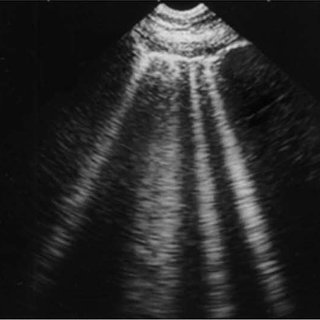

🌟B-lines